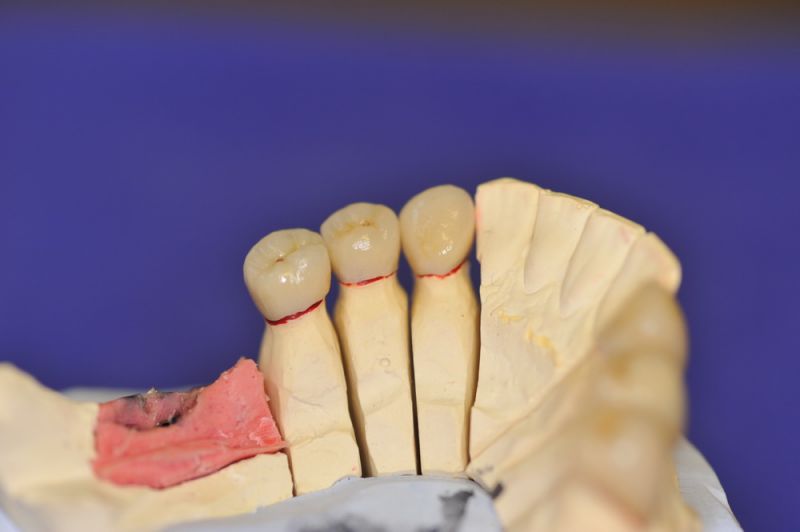

3. Sehr dünne Implantate, die von ursprünglich zwei je Kieferhälfte auf letztendlich drei je Kieferhälfte umgeplant werden mussten.

4. Notwendigkeit die Mundhygienefähigkeit der Arbeit auch unter sehr beengten Verhältnissen zu schaffen, um der Arbeit eine günstige Prognose mitzugeben.